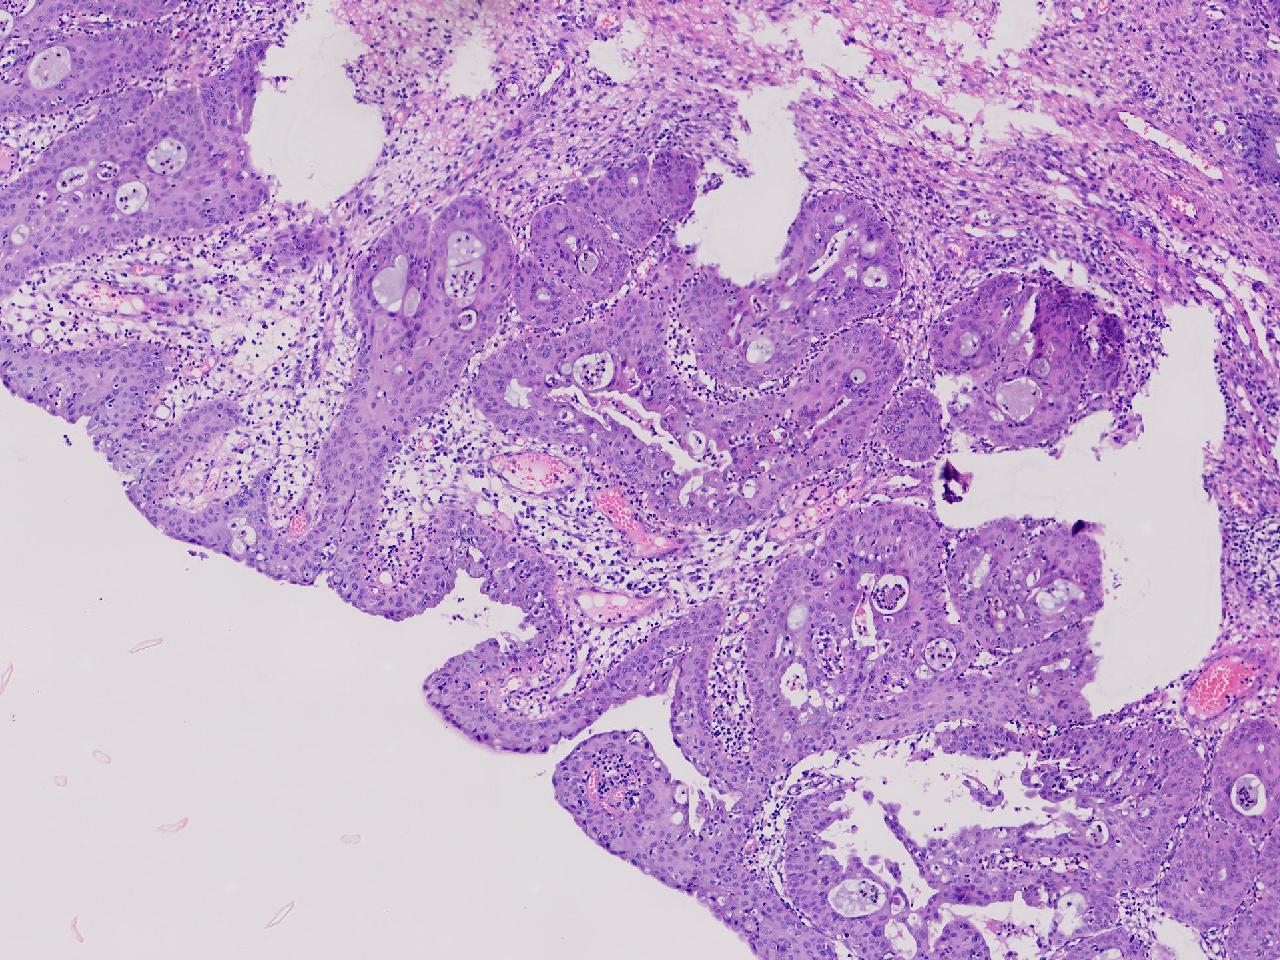

性别年龄42岁临床诊断宫颈赘生物

一般病史女,42岁,妇检时发现宫颈赘生物,大小0.2cmx0.5cm

标本名称管状赘生物

大体所见灰白色不整形软组织2块,一个直径0.3厘米,一个直径0.2厘米。

炎症

低级别诊断需要有个尺子,这个尺子就是“似是而非为非”,这个连似是而非都达不到。

有非典型鳞化,建议HPV检测

慢性宫颈炎伴腺上皮鳞化。